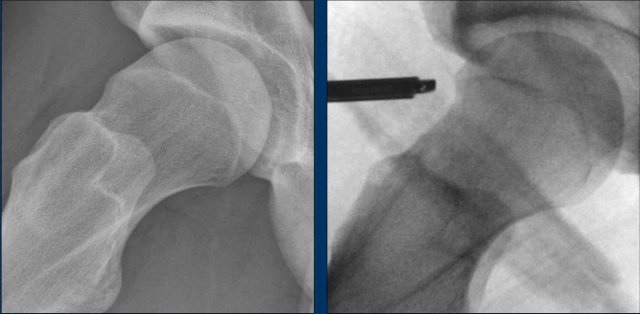

Images

In a patient with Cam morphology, the effect of reshape of the femoral head-neck junction is seen (arrow).

Initially, the patient was treated conservatively with physiotherapy, but this did not lead to satisfactory results.

An arthroscopic procedure was then performed, involving a reshaping of the femoral head-neck junction (arrow), which resulted in significant improvement.